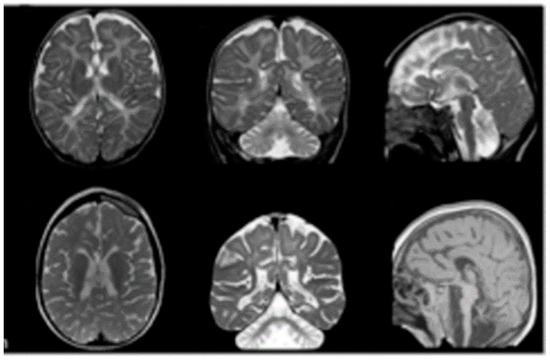

3.1. Case Report